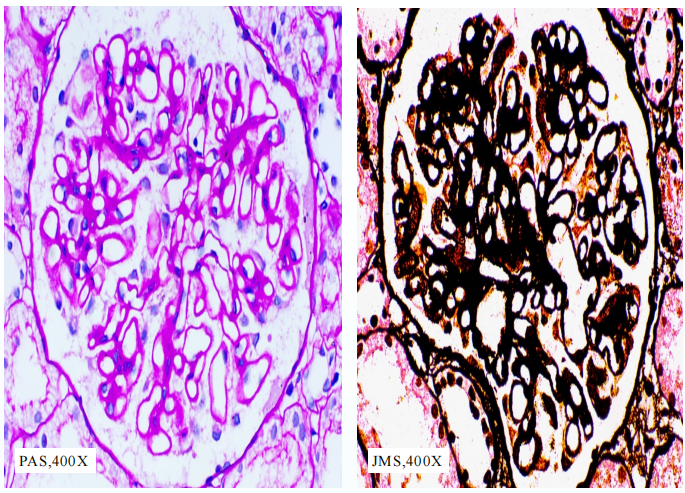

肾活检结果:光镜下可见膜性病变模式及肾小管间质慢性损害(图2);结合临床病史及免疫荧光(DIF)结果,继发性膜性肾病的可能性较大,同时可见高血压性血管改变。鉴别诊断:狼疮性肾炎(V型)?乙肝相关膜性肾病?

图2. 肾活检结果

免疫组化结果:肾组织HbsAg、HbcAg、HbeAg均阴性。

在狼疮与乙肝可能重叠的病例中,肾小球HBV抗原(尤其是HbeAg)的存在有助于确诊乙肝相关膜性肾病;因此,肾小球组织HbeAg阴性可否定乙肝相关膜性肾病的诊断。免疫组化因此有助于解决此类诊断困境。